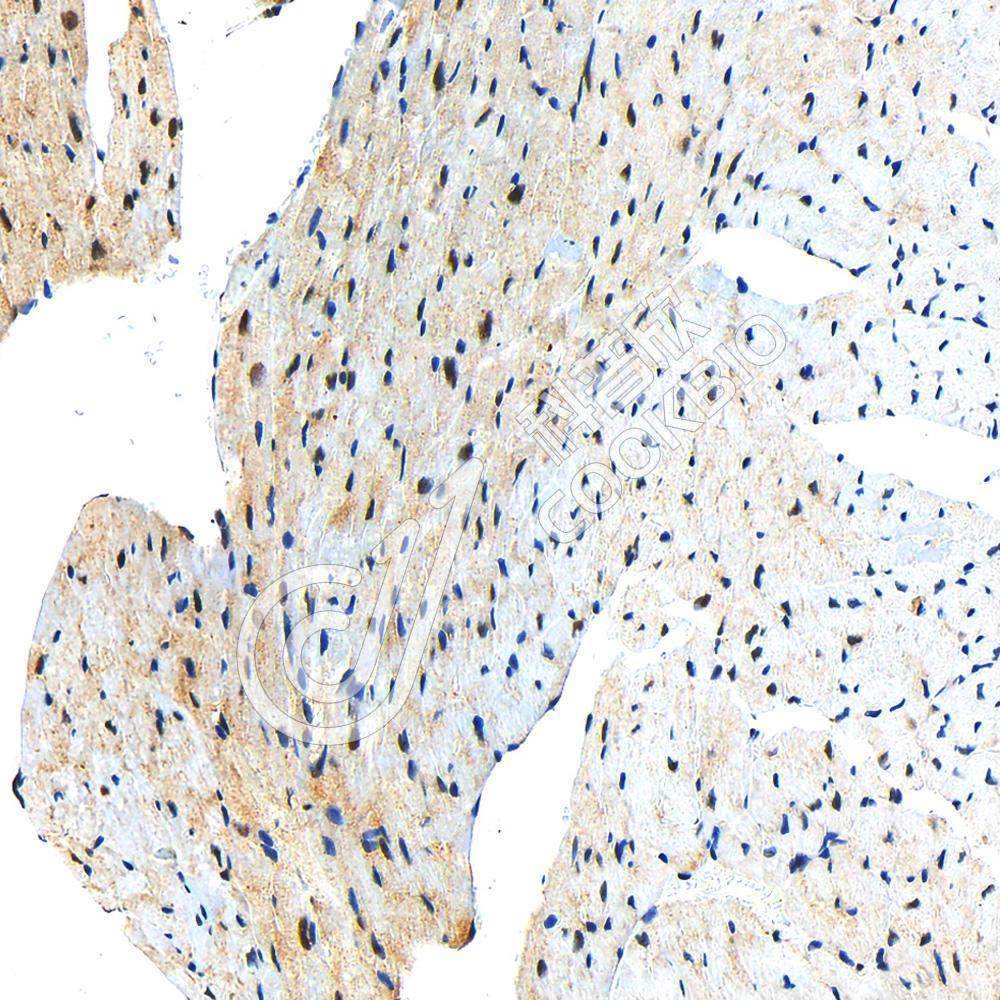

IHC检测Ubiquitin蛋白(货号 K1347100).

样品: 人肾, 4%多聚甲醛 (货号KSG1101) 固定12-24小时.

抗原修复: 柠檬酸抗原修复液(干粉, pH 6.0) (KSG1201), 98℃, 20分钟.

—抗: 1: 2300稀释, 4℃ 孵育过夜.

二抗: S-vision免疫组化多聚二抗(山羊抗兔),即用型 (货号KB3906), 室温孵育20分钟.